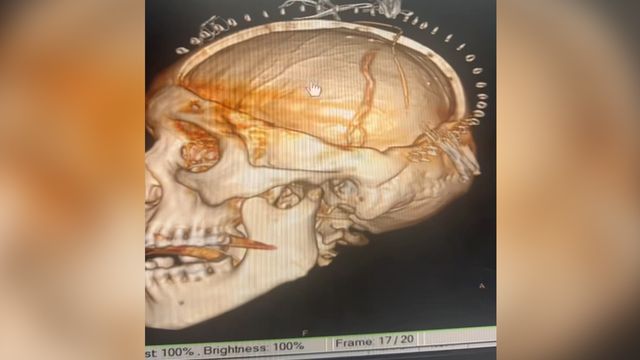

หมอสแกนสมอง พบเนื้อสมองบางส่วนตาย ตรงสีดำในภาพ CT แสดงว่าเกิน 8 ชั่วโมง ปกติคนเรามีเส้นเลือดไปเลี้ยงสมอง 4 เส้น คือ หน้าขวา หน้าซ้าย หลังขวา และหลังซ้าย แต่คนไข้รายนี้เส้นเลือดหายไปเหลือ 3 เส้น เกิดจากเส้นเลือดที่คอปริแตก ลิ่มเลือดไปอุดตันเส้นเลือดตัวเอง เนื่องจากคนไข้เส้นเลือดสมองตันในเวลากลางคืน เลยเวลาที่จะทำอะไรได้ จึงต้องผ่าตัดเปิดกะโหลกเพื่อลดแรงดันในสมอง